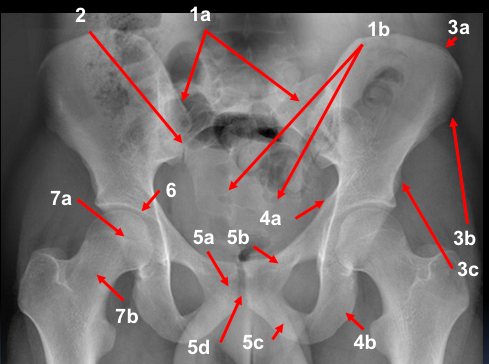

A 30 year old man was thrown from his motorbike at speed. His X-ray is shown.

What do you make of the X-rays? How would you describe the injury? What do think the mechanism of injury was? Any concerns about other structures that could potentially be injured? What would you do next?